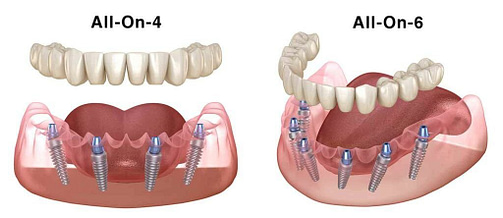

Considera questo: i nostri prezzi competitivi per trattamenti come l’All-on-4 a 6.900 euro e l’All-on-6 a 7.900 euro sono disponibili proprio a Seregno. Queste tariffe sono un’alternativa conveniente rispetto a viaggiare attraverso l’Europa alla ricerca di soluzioni dentali.

Considera questo: i nostri prezzi competitivi per trattamenti come l’All-on-4 a 6.900 euro e l’All-on-6 a 7.900 euro sono disponibili proprio a Seregno. Queste tariffe sono un’alternativa conveniente rispetto a viaggiare attraverso l’Europa alla ricerca di soluzioni dentali.